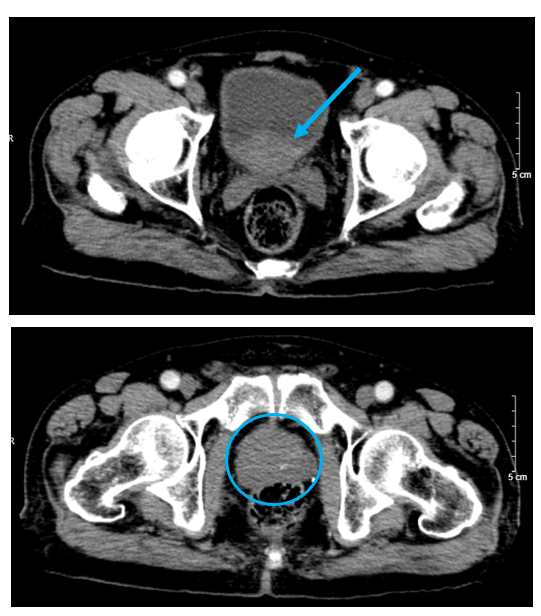

Hình 4. Tuyến tiền liệt tăng kích thước (hình tròn màu xanh), có phần lồi vào bàng quang (mũi tên xanh) trên phim chụp cắt lớp vi tính ổ bụng thì động mạch.